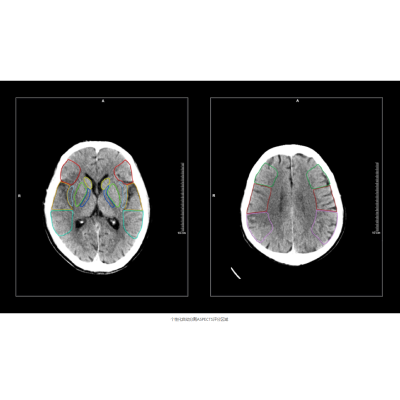

搭载该算法的联影智能CT脑缺血智能分析系统可精确分割并定位ASPECTS评分区域,自动提供左、右脑ASPECTS评分并标记早期缺血改变区域,提供ASPECTS评分预后参考指南及随访分析,帮助医生提高阅片准确度和一致性,将评分时间从几分钟缩短至几秒钟,把握治疗黄金时机。

病例展示

某三甲医院,一女性患者因突发左侧肢体无力、失语和双眼凝视等症状入院。

医生基于一站式CT扫描结果以及脑缺血AI分析,诊断该患者存在脑缺血情况,右脑ASPECTS评分为6分,有4个受影响区域。值得注意的是,该患者的豆状核和岛叶区域存在缺血问题,但由于早期征象不易识别,医生借助AI辨别发现出这两处区域的缺血情况。